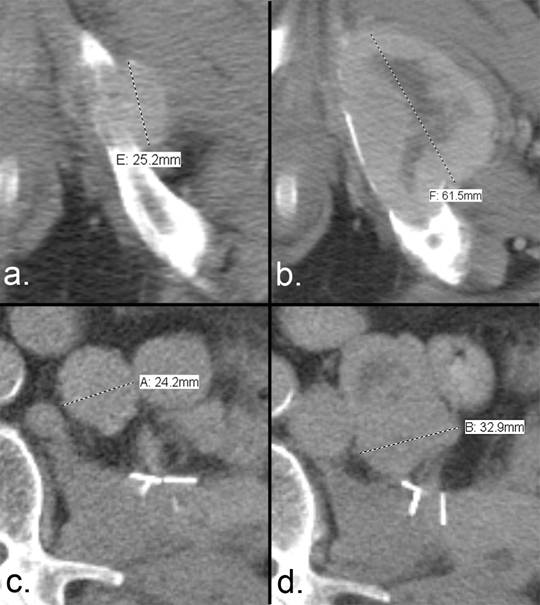

According to RECIST 1.1, drug efficacy is primarily determined by the sum of the measurements of the greatest longitudinal dimension of each target lesion. One of the differences between RECIST and RECIST 1.1 is that bone metastases with soft tissue masses measuring ≥ 10 mm are now accepted as target lesions. The soft tissue component is to be measured in an identical manner to that used for other target lesions (Fig. 1). Measurements are to be made in the plane of acquisition (typically axial for CT unless isotropic reconstructions are performed). The largest lesions are preferred if they are clearly and reproducibly measurable (e.g. the largest well-defined lesion is preferred over larger, ill-defined lesions), and no previously irradiated lesion is eligible as a target lesion unless it demonstrates progression after irradiation. Therefore, a careful search of the medical record for previous therapeutic radiation exposure is indicated prior to the selection of a bone metastasis as a target lesion.

Measurement of disease progression using the RECIST 1.1 criteria. (a) Axial CT of the pelvis and abdomen of a patient with renal cell carcinoma demonstrates a bone metastasis in the left inferior pubic ramus. The soft tissue component is > 10 mm, and (b) the short-axis diameter of the left retroperitoneal lymph node metastasis is >15 mm; both are considered measurable according to RECIST 1.1. The sum of the longest diameters is used to assess tumor response. (c) The bone metastasis has increased from 25.2 mm to 61.5 mm, and (d) the nodal metastasis has increased from 24.2 mm to 32.9 mm. The sum of the 2 lesions at the first time point is 49.4 mm, and the sum at the second time point is 94.4 mm. This increase of 91% exceeds the required > 20% increase that is necessary to qualify for the progressive disease category.